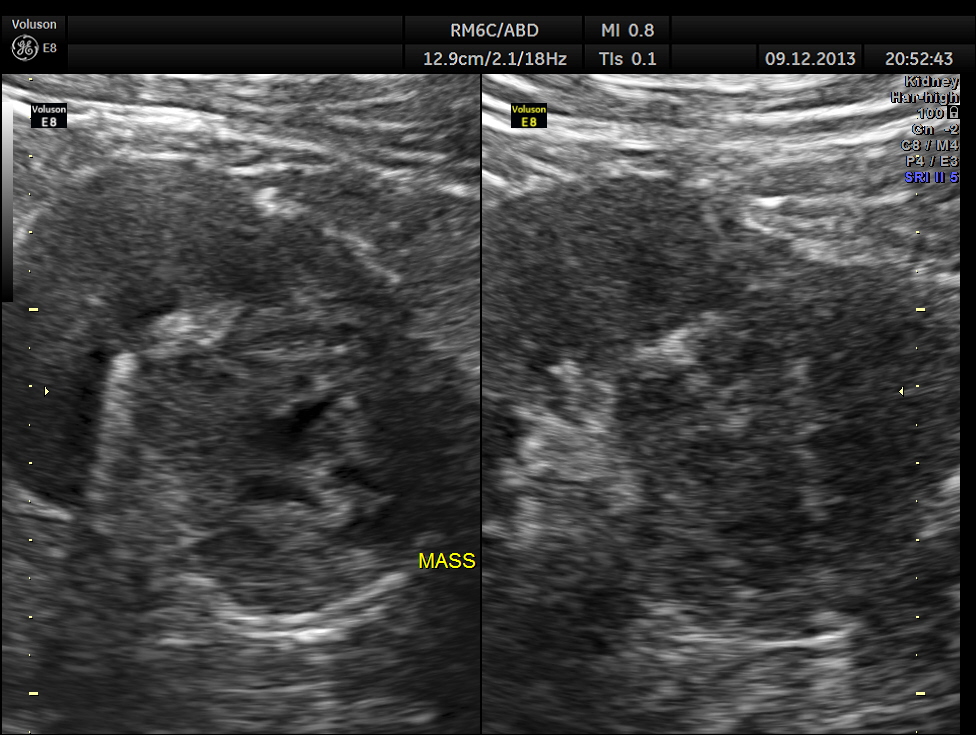

The pictures of the left kidney are given below. An echogenic mass lesion is seen .

Regular power doppler appears unremarkable.

Gray scale reconstruction of the mass is given below.